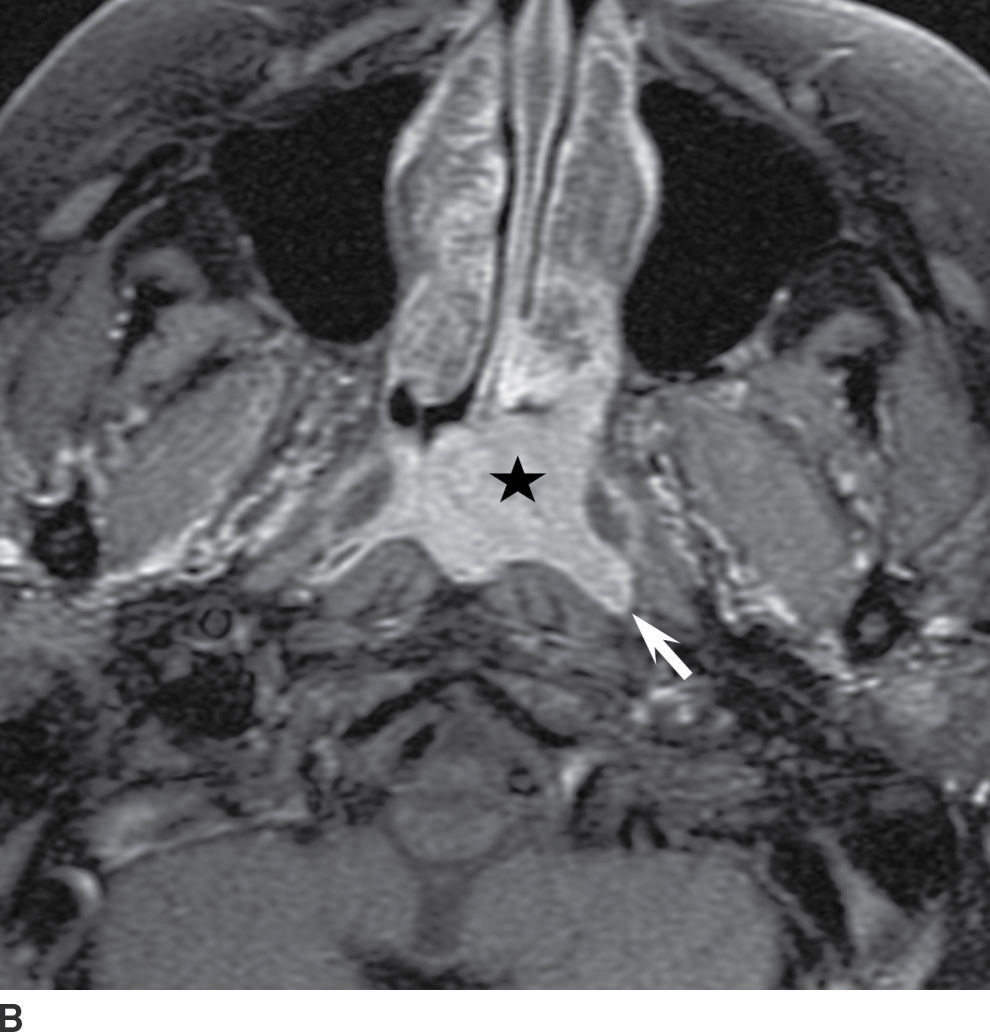

From radiologykey.com

Mucosal Cancers Neck Primaries and the Lymph Nodes Radiology Key Spine Cancer Neck Learning that you have a spinal tumor can be overwhelming. Some of the cancers that may involve the spine. Spinal metastasis (metastatic spinal cancer) happens when cancer in another part of your body spreads ( metastasizes) to. S pinal tumors can involve the neck, back and lower back. A spinal tumor is an abnormal growth of cells within or surrounding. Spine Cancer Neck.

Mucosal Cancers Neck Primaries and the Lymph Nodes Radiology Key Spine Cancer Neck A spinal cord tumor, also called an intradural tumor, is a spinal tumor that that begins within the spinal cord or the covering of the spinal cord (dura). Learning that you have a spinal tumor can be overwhelming. But you can take steps to cope after your diagnosis. A spinal tumor is an abnormal growth of cells within or surrounding. Spine Cancer Neck.

Mucosal Cancers Neck Primaries and the Lymph Nodes Radiology Key Spine Cancer Neck Most spinal cancer occurs inside the spinal column and usually doesn’t affect the spinal cord. A spinal cord tumor, also called an intradural tumor, is a spinal tumor that that begins within the spinal cord or the covering of the spinal cord (dura). Learning that you have a spinal tumor can be overwhelming. Some of the cancers that may involve. Spine Cancer Neck.